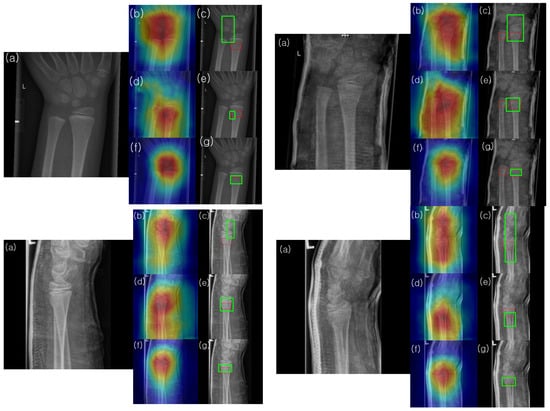

4.4. Extracting Heatmaps and Predicting Bounding Boxes

Gradient-weighted class activation mapping (Grad-CAM) was utilized to identify the network’s area of focus and predict the fracture site accordingly. The gradient of the class score was computed with respect to the feature maps in the final convolutional layer. Each feature map was then weighted based on the gradient’s strength, and these weighted feature maps were summed to generate a heatmap. The resulting heatmap was normalized to a range between 0 (representing lows) and 255 (representing highs) using the peaks and troughs and was visualized as a jet color map, in which blue indicates the lowest activation, and green to red represents increasingly higher activation levels. Squares with an activation value above a certain threshold (230 in our case) were marked as potentially indicating fractures. These were compared to the squares marking the fracture site as annotated by the medical expert. As depicted in Figure 7, the far-left image is the input fracture image, the middle image overlays the original image with the heatmap, and the far-right image shows the predicted fracture site based on our threshold criterion.

Figure 7. Heat-map extracted from the HyperColumn-CBAM-Densenet169 model, with the green box indicating the ground truth fracture region.